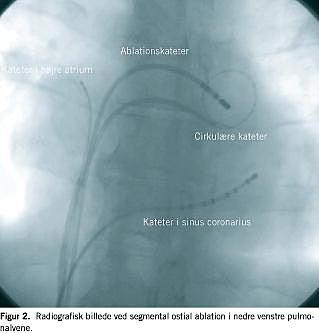

Triggerablation er rettet mod pulmonalvenerne som det primære område for initiering af AF. Proceduren kan udføres ved tre forskellige teknikker: 1) fokal ablation: ablationskatetret føres skiftevis ind i pulmonalvenerne med energitilførsel mod påviste arytmifoci i sleeves. Teknikken er imidlertid omstændelig, da det er nødvendigt med samtidig tilstedeværelse af supraventrikulære ekstrasystoler udgående fra pulmonalvenerne. Fokal ablation anses i dag for at være obsolet, da den er smertefuld og forbundet med en lavere succes- og højere komplikationsrate (særlig pulmonalvenestenose) end de øvrige teknikker [31]. 2) Segmental ostial ablation: Ved proceduren benyttes der to styrbare katetre: et cirkulært kateter til kortlægning af de elektriske potentialer i sleeves i lungevenens ostium og et ablationskateter. Det cirkulære kateter er distalt udstyret med ti elektrodepoler. De to katetre placeres i hver af de fire pulmonalveneåbninger (Figur 2 ). Ved detektion af elektriske potentialer som udtryk for elektrisk kontinuitet mellem venstre atrium og pulmonalvenen foretages der ablation af det ostiale myokardiale segment med tidligst aktivering for at isolere pulmonalvenerne fra venstre atrium. 3) Cirkumferentiel ablation: Vha. et elektromagnetisk computersystem konstrueres en tredimentional model af venstre atrium med pulmonalvener. Herefter foretages der cirkulære ablationslinjer omkring henholdsvis de to højre- og de to venstresidige pulmonalvener, proksimalt for indmunding af pulmonalvenerne i venstre atrium (Figur 3 ). Hensigten er at isolere samtlige pulmonalvener i forhold til atriet uanset tilstedeværelse af elektriske potentialer.